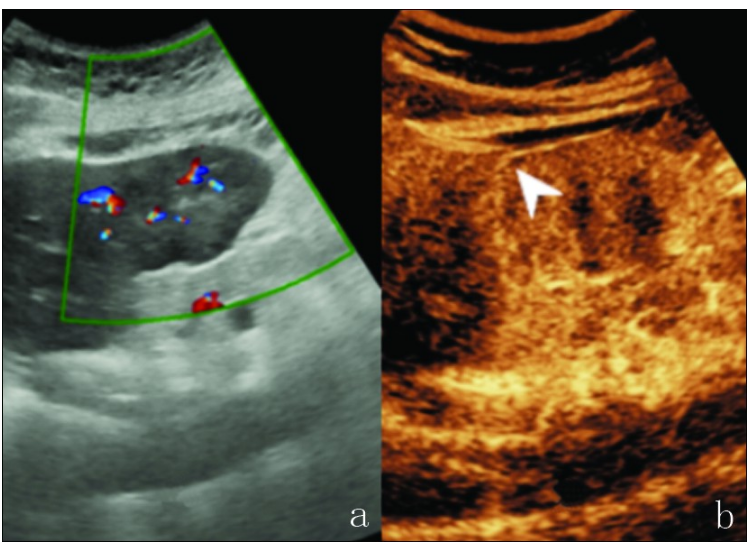

患者,女性,45岁,因体检发现肝占位1年余入院。患者发病以来偶有右上腹隐痛。入院后检查:甲胎蛋白(alpha-fetoprotein, AFP)等肿瘤指标无异常。常规超声:肝左外叶下段见45 mm×31 mm不均质低回声团块,边界欠清,向表面突起,彩色多普勒示病灶内部较丰富彩色血流。

超声造影:肝左外叶病灶13 s开始增强,26 s达峰值,呈不均匀高增强,周边包膜样增强,48 s部分病灶增强开始减退,门脉期及延迟期均呈等回声及稍低回声改变,血管后相呈低回声改变,提示肝左叶实质占位,考虑肝脏恶性肿瘤可能大,见图1。

图1 肝脏淋巴上皮瘤样胆管细胞癌超声图像。a.病灶彩色多普勒血流成像;b.病灶延迟期高增强环表现(白色箭头所示)。

本例病灶在动脉期呈整体不均匀高回声增强,门脉期和延迟期病灶内部增强回声减退,周边增强回声轻度减退呈高增强环表现。病变在超声造影门脉期、延迟期形成高增强环的原因可能是不同细胞组织结构导致的差异。